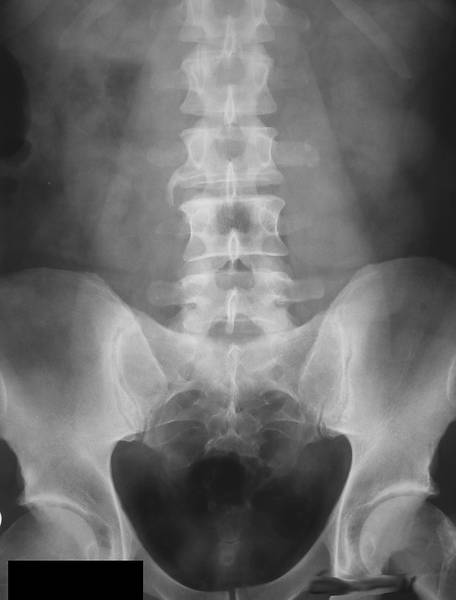

ОБЗОРНЫЙ СНИМОК

Любое рентгенологическое исследование в урологии необходимо начинать с обзорного снимка мочевой системы (рис.).

Обзорный снимок органов мочевой системы.

Интерпретацию обзорного снимка начинают с рассмотрения костного скелета: поясничных и нижних грудных позвонков, рёбер, тазовых костей. Иногда на нём удаётся увидеть тени почек, которые расположены слева между телом XII грудного и II поясничным позвонком, справа — между верхним краем I поясничного позвонка до тела III поясничного позвонка. Следует обращать внимание на их форму, величину и контуры, изменение которых позволяет заподозрить патологический процесс в почках. В норме тень правой почки несколько короче и шире левой. Это связано с разным углом наклона вертикальной оси почек по отношению к позвоночнику. Нужно обратить внимание на степень плотности тени, как по всей её площади, так и в отдельных сегментах. Далее обращают внимание на тень поясничных мышц (m. psoas). В норме она имеет вид усечённой пирамиды, вершина которой расположена на уровне тела XII грудного позвонка. Изменение или исчезновение контуров этой мышцы на одной из сторон наблюдают при воспалительных или опухолевых процессах в забрюшинном пространстве. Отсутствие тени поясничных мышц при травме почки свидетельствует о наличии урогематомы в забрюшинном пространстве.

Мочеточники в норме на обзорном снимке не видны. Иногда, если мочевой пузырь наполнен насыщенной мочой, заметна его тень. В норме на обзорном снимке он имеет форму эллипса.

После оценки естественных структур обращают внимание на наличие добавочных теней. Они различаются по форме, величине, контрастности, однородности. Часто на рентгенограмме видны просветления, обусловленные кишечными газами.